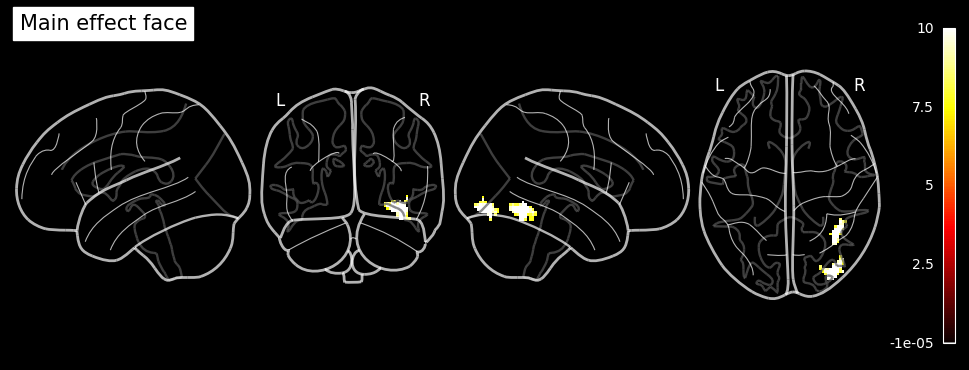

Citation:

Wakeman, DG and Henson, RN (2021). Multisubject, multimodal face processing. OpenNeuro. [Dataset] doi: 10.18112/openneuro.ds000117.v1.0.5

Wakeman, D.G. & Henson, R.N. (2015). A multi-subject, multi-modal human neuroimaging dataset. Sci. Data 2:150001 doi: 10.1038/sdata.2015.1

The fMRI dataset used for this example is part of a multi-subject, multi-modal (sMRI, fMRI, MEG, EEG) neuroimaging dataset on face processing. It contains data in BIDS format on sixteen healthy volunteers. The data was recoreded while the volunteers performed multiple runs of hundreds of trials of a simple perceptual task on pictures of familiar, unfamiliar and scrambled faces during two visits to the laboratory.

The facial stimuli consisted of two groups of 300 greyscale photos, half of which were of famous people and half of which were of non-famous people (unknown to the participants). Each scrambled face was created either from the famous face or the non-famous face of the same stimulus number. Additionally, each image was presented twice to the participants. The second presentation occurred either immediately after the first presentation (Immediate Repeats) or after 5–15 intervening stimuli (Delayed Repeats), with 50% of each type of repeat. To ensure that each stimulus received equal attention, participants were instructed to use their left or right index finger to press one of two keys (assignment counter-balanced across participants). They determined the symmetry of each image by pressing a key based on whether they perceived it to be ‘more’ or ‘less symmetric’ than average.

In the original paper (Wakeman & Henson, 2015), the repetition manipulation was not distinguished, meaning that initial and repeated presentations were treated identically without considering the timing of the repeats.

To illustrate the setup of a 3x2 factorial design analysis (familiar vs. unfamiliar vs. scrambled faces) x (1st vs. 2nd presentation) in an SPM Nipype workflow, the event files will be adapted accordingly. Each stimulus type will be labeled as either the first or second presentation. However, for simplicity, no distinction is made between immediate and delayed repetitions, resulting in 6 stimulus types (conditions): Familiar-Rep1 (F1), Familiar-Rep2 (F2), Unfamiliar-Rep1 (U1), Unfamiliar-Rep2 (U2), Scrambled-Rep1 (S1), and Scrambled-Rep2 (S2).

contf2 = ['Main effect Face', 'F', [face1, face2]]

contf3 = ['Main effect Rep', 'F', [rep1]]

contf4 = ['Interaction: Face x Rep', 'F', [int1, int2]]

contrasts = [contf1, contf2, contf3, contf4, cond1, face1, face2, rep1, int1, int2]